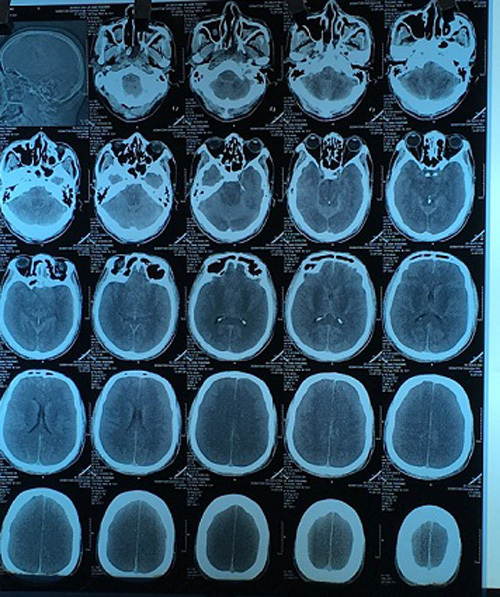

| Nhập viện muộn, não bệnh nhân căng phù 2 bên |

Kết quả chụp phim cho thấy: não bị phù, căng cả 2 bên, nhu mô não tổn thương nặng và lan rộng cả 2 bên.